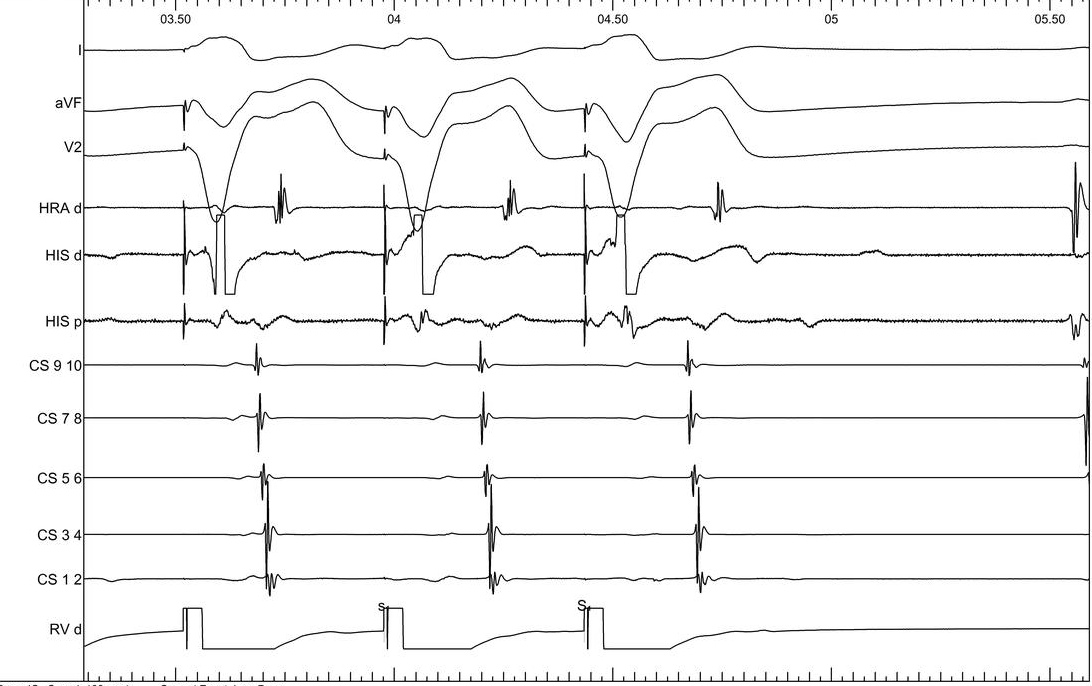

Single ventricular extrastimulus

02_rv_600_300.jpg